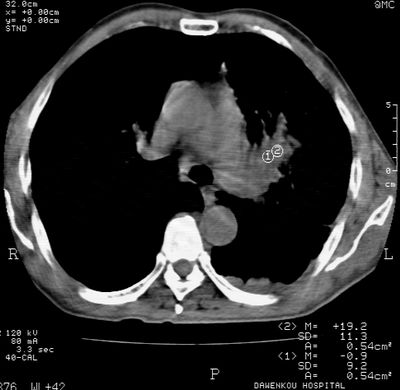

标题: CT24000:M65,胸痛,胸闷月余,既往慢支,肺气肿,肺心病 [打印本页]

标题: CT24000:M65,胸痛,胸闷月余,既往慢支,肺气肿,肺心病

左肺门肿块,相应支气管闭塞,左肺上叶、舌叶大片及散在高密度影,部分呈不张改变,两肺纹粗乱,左侧胸腔积液。考虑左侧中央型肺癌伴阻塞性改变。

左肺门见巨大软组织肿块影,直径约--,境界清,左上肺叶支气管变窄,左上肺舌叶见大片状密实影,余肺纹理增多、紊乱、纤细、部分网格状,两肺透亮度增高,纵隔内见增大多发淋巴结影,心影略左偏,左侧少量胸腔积液。

左侧中央型肺癌伴左上肺舌叶不张、纵隔淋巴结转移,左侧少量胸腔积液。